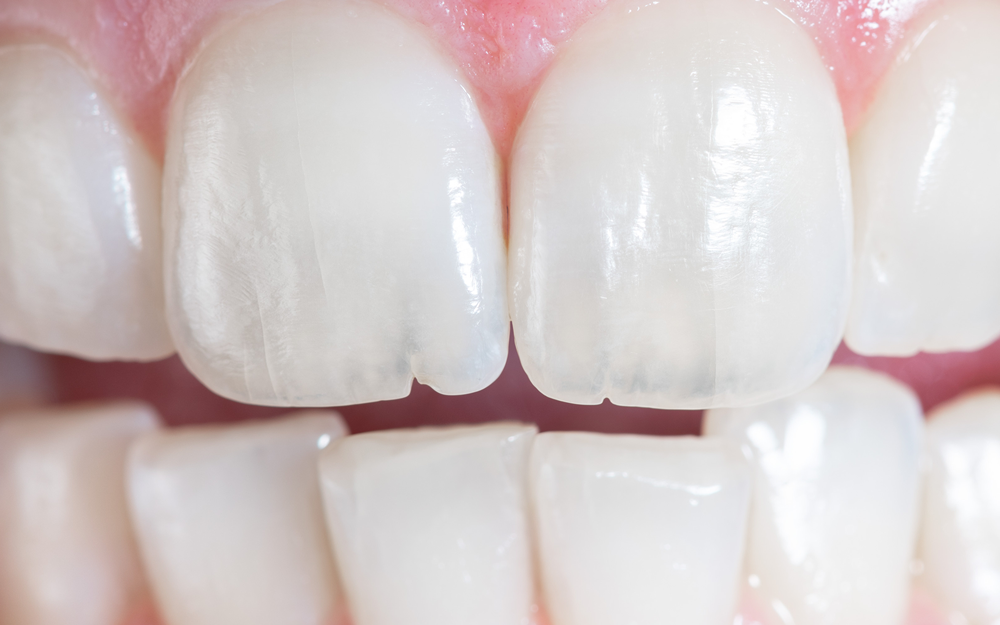

치아균열

· 평소엔 괜찮다가 음식을 씹는 특정 지점에서만 날카로운 통증이 온다.

· 특히 딱딱하거나 질긴 음식을 씹었다가 뗄 때 통증이 더 심하다.

· 통증이 순간적으로 '찌릿' 하고 나타났다가 사라진다.

· 차가운 물을 마실 때도 시큰한 느낌이 들 수 있다. (균열 틈으로 물이 스며듦)

· 겉으로 보기엔 아무 이상이 없어 보인다.

STEP 01. 치아 표면에 국한된 균열

증상 : 씹는 면에 실금처럼 보입니다. 통증이 거의 없습니다.

치료 : 강한 치아 저작과 이악물기 등의 악습관 인지 후

습관 개선이 필요하며, 원내에서 교육 및 경과 관찰합니다.